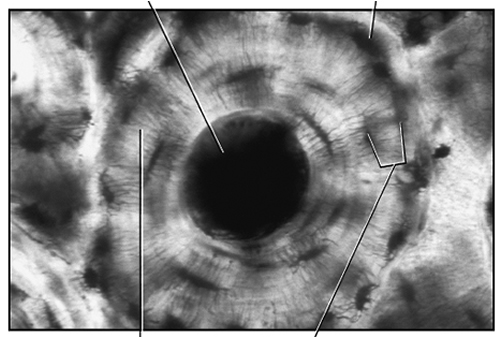

: Ground Bone

10X

40X